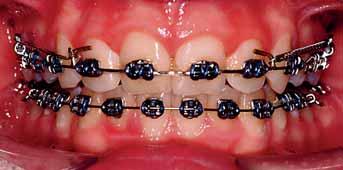

3. Anterior bite plan to reduce the overbite and bonding the lower arch (Figure 5).

The oral hygiene of the patient and the carious lesions were addressed prior to the start of the fixed appliances treatment. The patient’s compliance was good and treatment progressed without encountering major problems. The reduction of the overbite was achieved initially with the anterior bite plane then a reverse curve of Spee was placed in the lower archwire to control the overbite. A Trans-Palatal Arch (TPA) with Nance button was fitted prior to the extraction of the upper premolars in order to reinforce the anchorage (Figure 6). The treatment continued with the use of Class II traction on both sides and space closure mechanics.

The next phase of treatment involved the fitting of the Trans-Palatal Arch (TPA) and the removal of the upper first premolars. Because of the increased overjet, this was a case of maximum anchorage and any mesial movement of the upper buccal segments was not desirable (Figure 6). It remains equivocal in the literature whether TPA appliances can provide anteroposterior anchorage. In fact, recent evidence suggested the contradictory 8 Alternatively the anchorage issue in this case could have been addressed with a Temporary Anchorage Device. The increase

The space closure phase of treatment was conducted carefully in order to prevent anchorage loss (Figure 7). Traditionally, clinicians retract the canines until they are in Class I relationship then the retraction of the incisors is followed. On theoretical grounds, retracting all six teeth together simultaneously would be expected to increase anchorage demands although this increase is not apparent clinically. However, some clinicians choose to retract all six together for two reasons namely simplicity and to avoid retracing steps of tooth movement. It is debatable which method is better but in this case, retracting all six anterior teeth as a block was adopted.